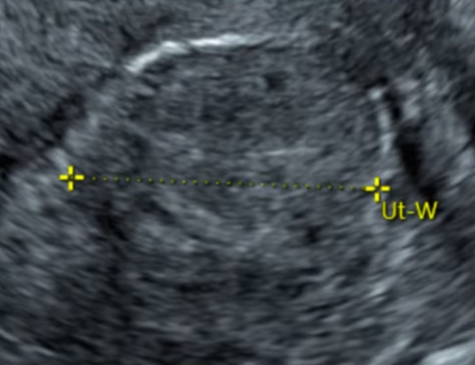

肌瘤类型和位置经评估适合做USgFUS。